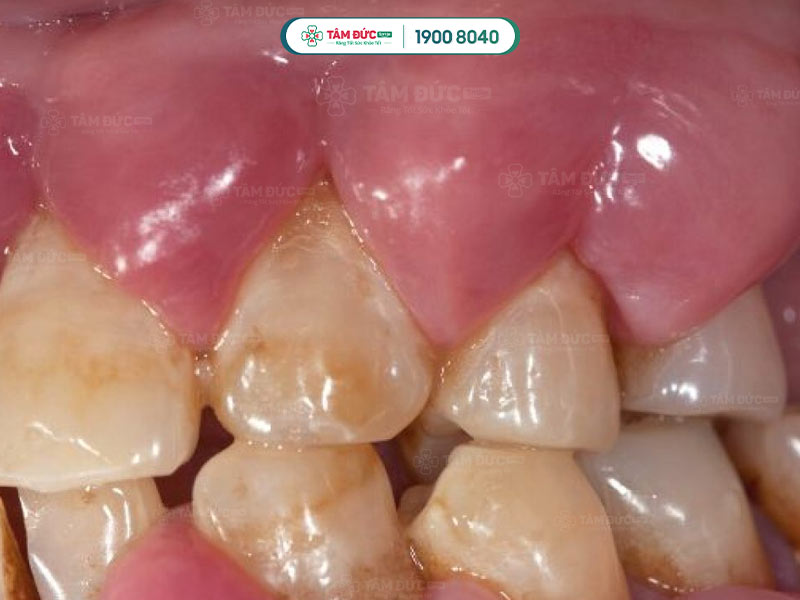

1.2.3. Áp xe nha chu

- Xảy ra khi vi khuẩn xâm nhập qua các lỗ nhỏ trên răng và nướu.

- Thường do các mảng bám tích tụ dọc theo đường viền nướu và cứng lại thành cao răng.

- Các cao răng này tích tụ gây kích ứng mô nướu, dẫn đến viêm và nhiễm trùng nướu. Khi viêm bắt đầu trở nên nghiêm trọng, mô nướu chết dần và xảy ra mất xương.

- Nhiễm trùng nha chu nặng làm nướu tách khỏi chân răng, làm răng lung lay và gãy rụng. Quý khách cần điều trị nhiễm trùng nha chu sớm để ngăn ngừa nhiễm trùng lan rộng gây mất răng.